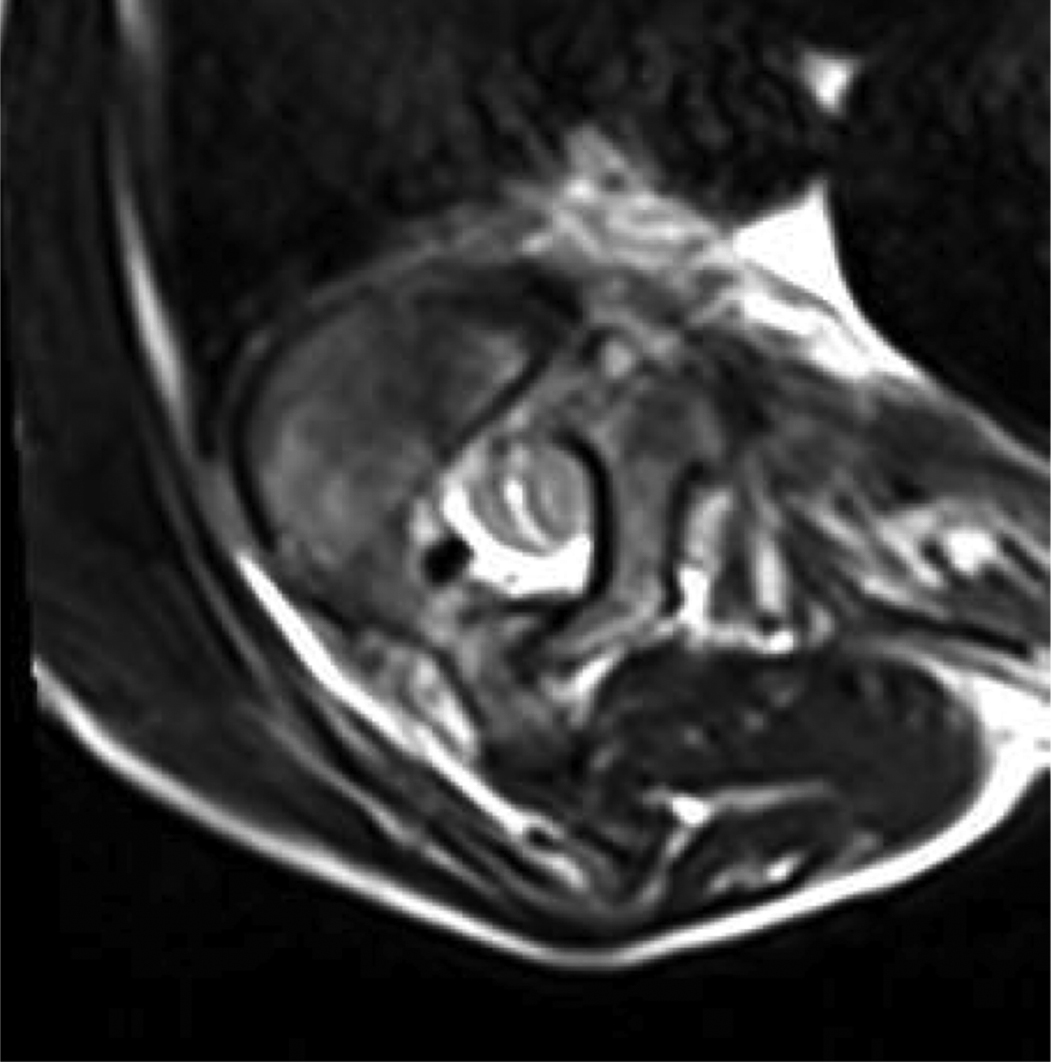

Sielatycki et al. classified the morphology of the spinal cord within the spinal canal based on the presence of cerebrospinal fluid (CSF) between the neural elements and the pedicle wall as well as any deformity imparted by this pedicle on the spinal cord. Type 3 spinal cords, defined as those with no CSF between the spinal cord and pedicle and deformity/flattening of the cord, were found to have a 28-fold higher rate of losing IONM data intraoperatively (Figure 2).22

Figure 2. Cross sectional T2 weighted MRI of the apical vertebrae from the child in Figure 1. The spinal cord is compressed against the pedicle wall with no intervening CSF. There is no significant flattening of the cord, consistent with a type 2 spinal cord.